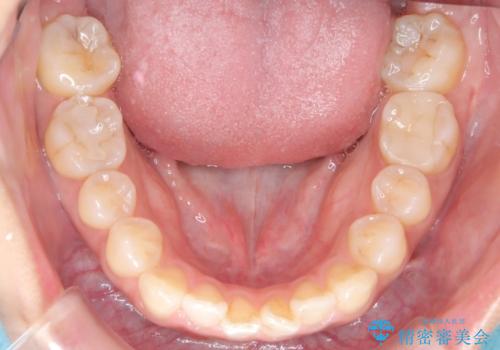

- 患者様は、奥歯(臼歯部)の反対咬合を主訴に来院されました。反対咬合は、噛み合わせのズレや顎の成長に影響を与える可能性があるため、早期の治療が重要です。診断の結果、上顎の幅が不足していることが原因と判明し、MARPE(骨固定式上顎急速拡大装置)を用いて上顎を広げる治療を計画しました。その後、歯列の調整のために審美ワイヤー矯正を行う方針としました。

MARPEを使用して上顎を拡大し、適切な歯列のスペースを確保しました。この拡大によって、反対咬合が改善され、正常な噛み合わせへと誘導できました。その後、目立ちにくいブラケットと白いワイヤーを使用した審美ワイヤー矯正を行い、歯列を整えました。治療が進むにつれ、噛み合わせのバランスが良くなり、見た目も自然な仕上がりに。

患者様からも「しっかり噛めるようになり、見た目も気にならなくなった」と満足の声をいただきました。